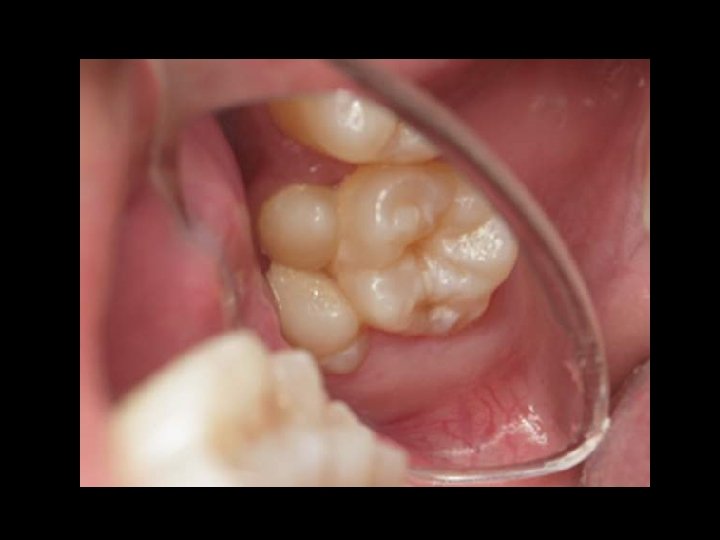

Occlusal View • Rhomboidal geometric form – Acute MB and DL corners – Obtuse DB and ML corners • 5 -sided (pentagonal) • Largest F-L dimensions of any tooth

Occlusal view… • F-L and M-D dimensions more similar* • M-D width as wide or wider lingually than facially* • Four major cusps: ML, MB, DL (largest to smallest) • Cusp triangle: MB, DB, ML (trigon)

Occlusal view… • Transverse ridge – Triangular ridges of MB and ML cusps • Oblique ridge – Triangular ridges of DB and ML cusps (distal cusp ridge? ) – About same height as the marginal ridges*

Occlusal view… • Three pits: mesial, central, distal • Three primary developmental grooves: central, buccal, distolingual • Four fossae: mesial, central, distolingual